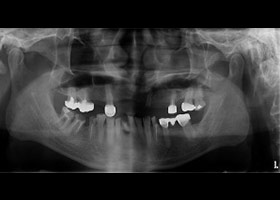

病患:55歲 男性

主訴:多顆缺牙,想全口治療。

診斷:

多顆缺牙、牙周病、多顆蛀牙。

治療計畫:

經由多顆人工植牙及全瓷假牙的全口重建,牙周病治療讓病人恢復咬合的功能與美觀,也易於每日的清潔保養。

主治醫師:張登信 醫師